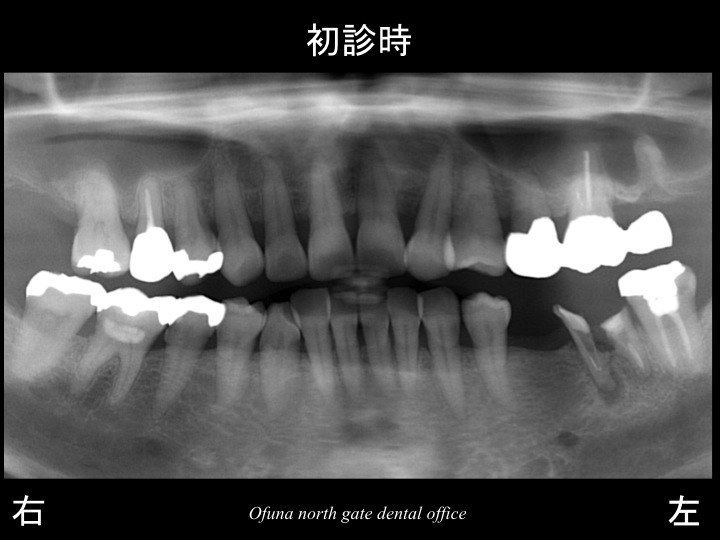

早速初診時のレントゲンから始めましょう!

初診時、下顎左側の奥歯が欠損しているため、治療法を聞きたく来院されました。

このようなケースが最も多いです。